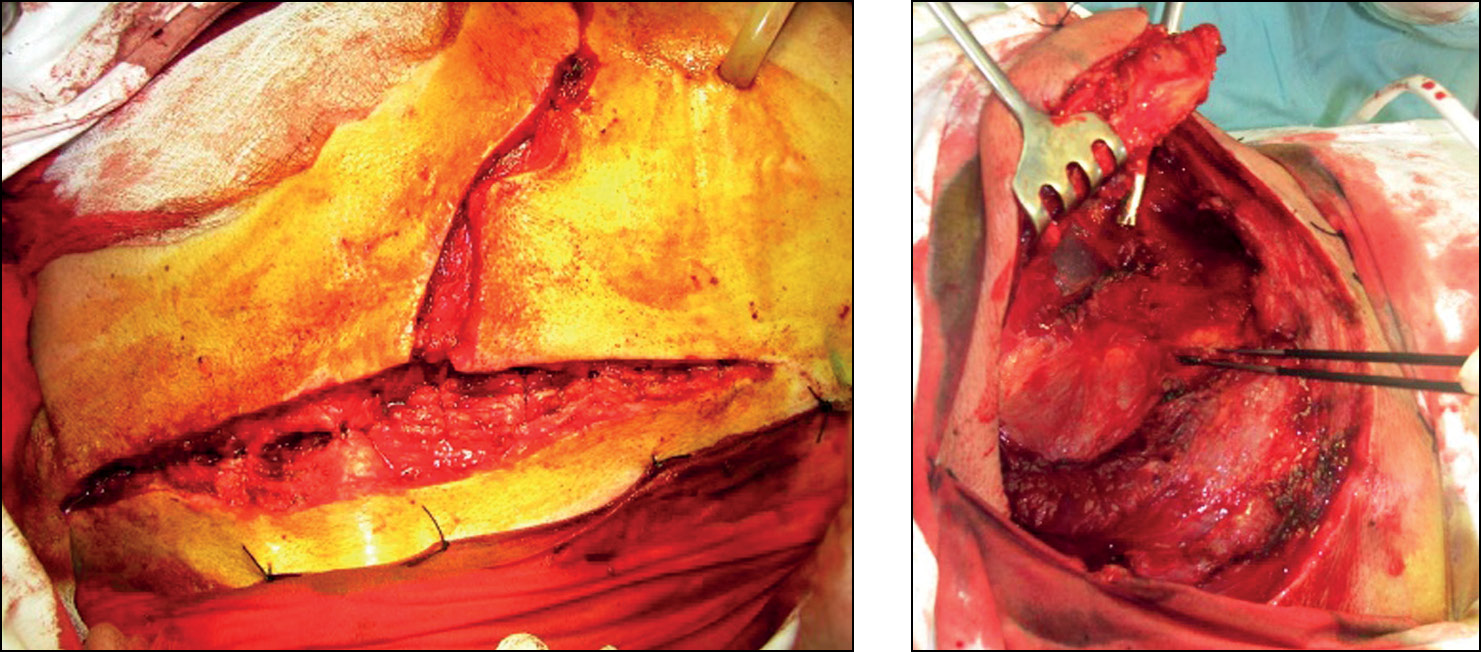

Выполнен косой разрез шеи вдоль внутреннего края грудино-ключично-сосцевидной мышцы с переходом на грудину (рис. 4).

Рис. 4. Разрез кожи и мягких тканей. Скелетирование рукоятки и тела грудины.

Fig. 4. Incision of the skin and soft tissues. Skeletonization of the manubrium and body of the sternum.

После скелетирования рукоятки грудины стернотомом (или с помощью пилы Джигли) выполняется поперечное рассечение грудины в месте соединения её рукоятки и тела, затем — продольное рассечение рукоятки (манубриотомия) и раздвигание её краёв (рис. 5).

Рис. 5. Проведение манубриотомии.

Fig. 5. Performing a manubriotomy.

При осторожном продвижении глубже появляются большие сосуды — плечеголовной ствол и плечеголовная вена, что хорошо визуализировано на схеме и операционных снимках (рис. 6).

Рис. 6. Выделение плечеголовного ствола и плечеголовной вены.

Fig. 6. Isolation of the brachiocephalic trunk and brachiocephalic vein.

Затем сложный и деликатный момент — мобилизация и отодвигание книзу крупных сосудов (левая плечеголовная вена и плечеголовной ствол аорты). При этом надо помнить, что стенка вены очень тонкая и легкоранимая, а возвратный гортанный нерв может быть тесно связан и неразделим с большими сосудами. Пищевод и трахея смещаются медиально, а плечеголовной ствол мобилизуется кнаружи. После рассечения предпозвоночной фасции в ране обнажаются передние поверхности тел Th1-Th4 позвонков (рис. 7).

Рис. 7. Передняя поверхность тел позвонков Th1-Th4.

Fig. 7. Anterior surface of the vertebral bodies Th1-Th4.